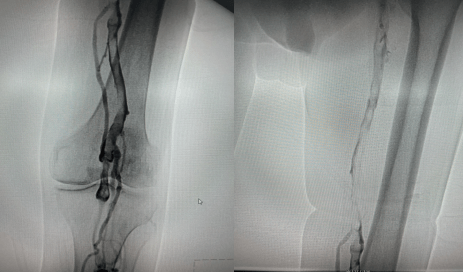

术中造影左下肢股静脉、腘静脉大量血栓形成

复查造影左下肢深静脉血流通畅,血栓完全消失